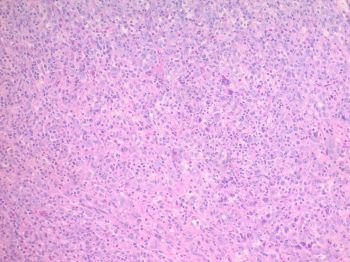

81-year-old female with a remote history of follicular lymphoma was undergoing evaluation for possible disease recurrence when an incidental right breast mass was identified.